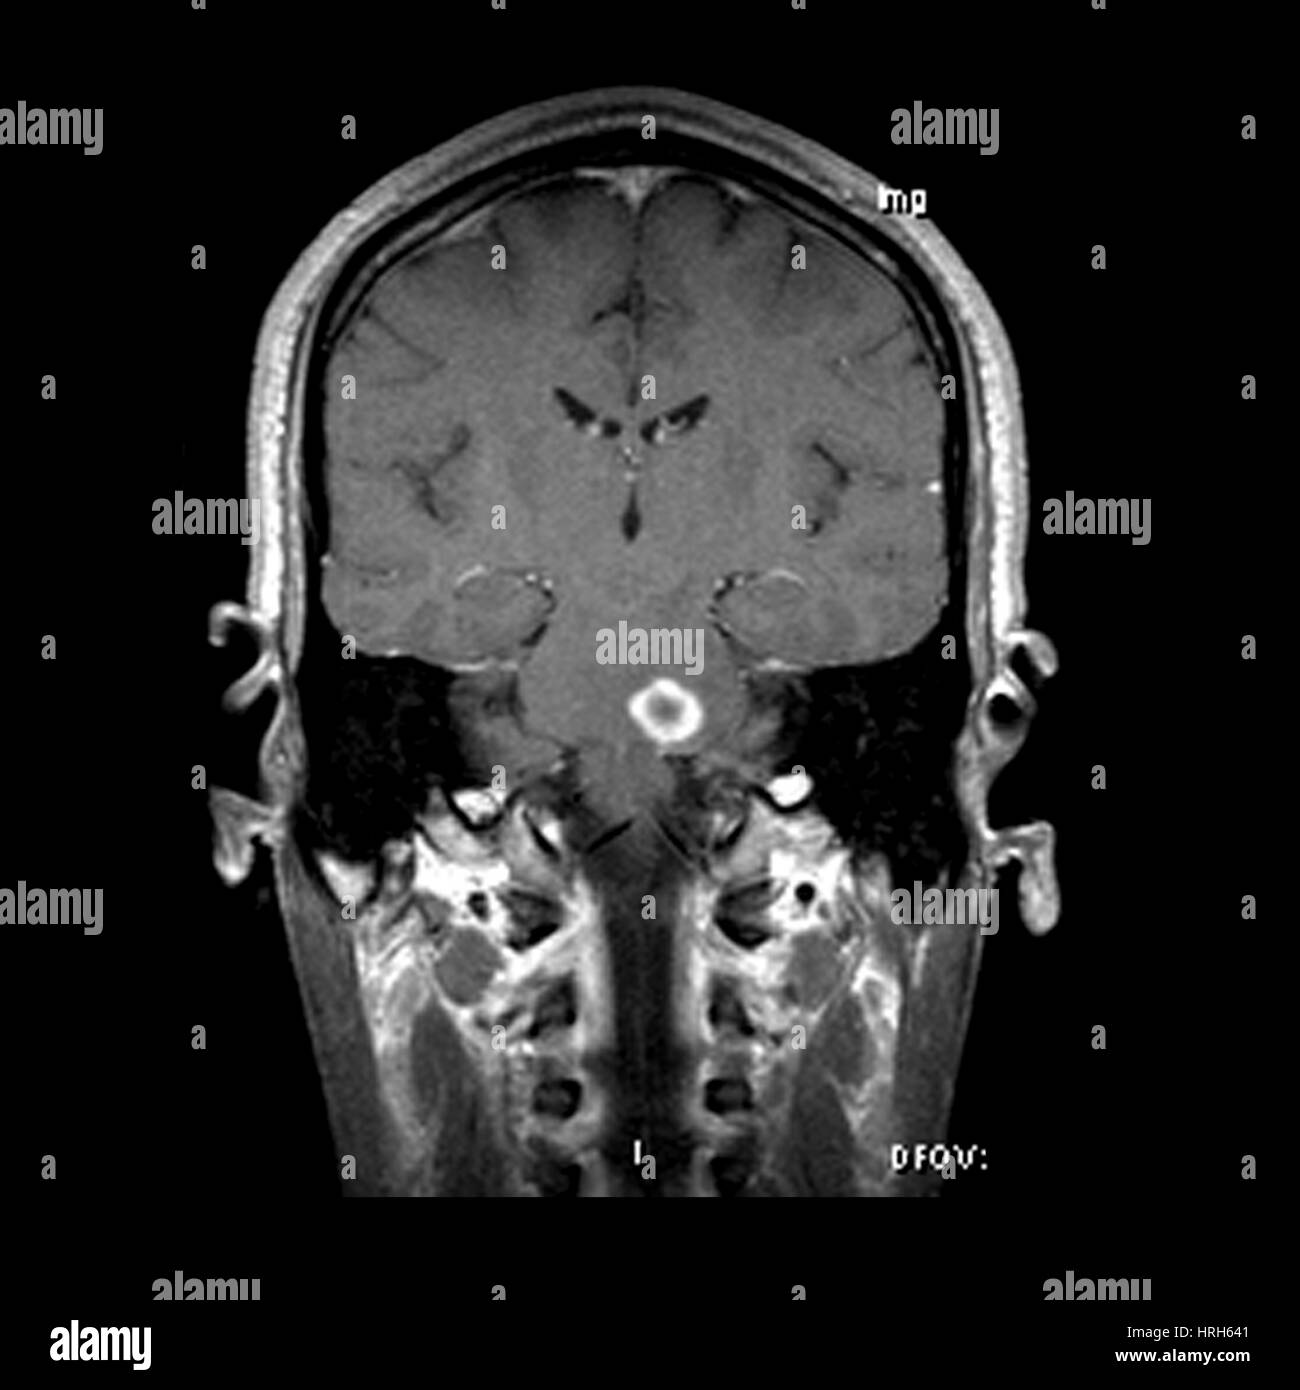

(11/26) MRT Schädel in Transversalebene, T₁‐gewichtet, FFE – DocCheck MS Herd MRT (1) – DocCheck

(16/34) MRT Schädel in Sagittalebene, T₂‐gewichtet – DocCheck MRT Bilder-Hubbel-??? Hilfe (Kopf)

MRT Schädel – DocCheck #MRT: Sungai Buloh – Kajang Line Phase 1 To Officially Start 16th December – Hype Malaysia

MRT 4 Schädel – DocCheck Taipei MRT Roadmap

MRT Schädel – DocCheck MRT Bild, könnte das ein Tumor sein? Kennt sich jemand damit aus? Könnte die helle Fläche ein …

MRT Schädel – DocCheck Sichere Prostatavorsorge mittels MRT-Untersuchung der Prostata